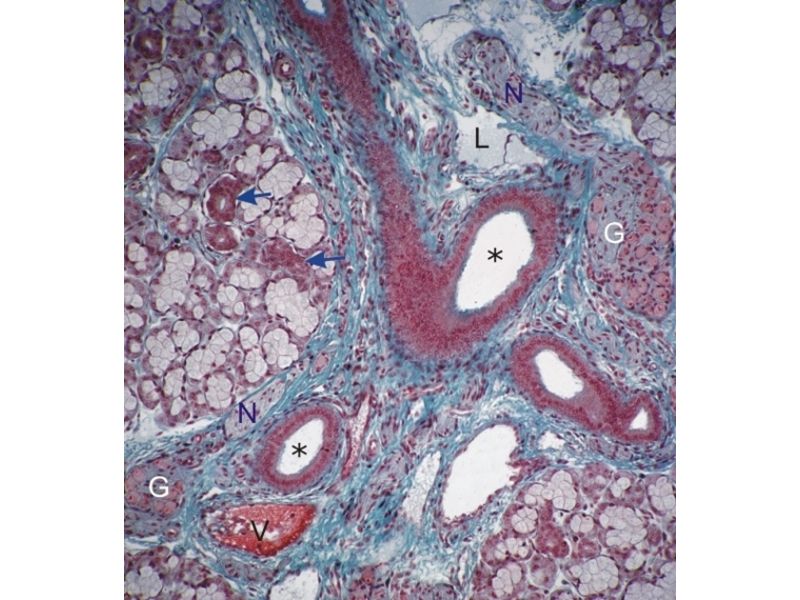

Fill in all the missing labels, and assess as you move through the slides. Answers on the down slide. It is important to do this using pen and paper, and not just glance through the images.